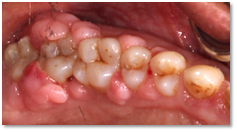

Before and after Periodontal Therapy

![]() | ![]() |

| Untreated severe gum disease | Gum disease treated and stabilised by Dr Halai |